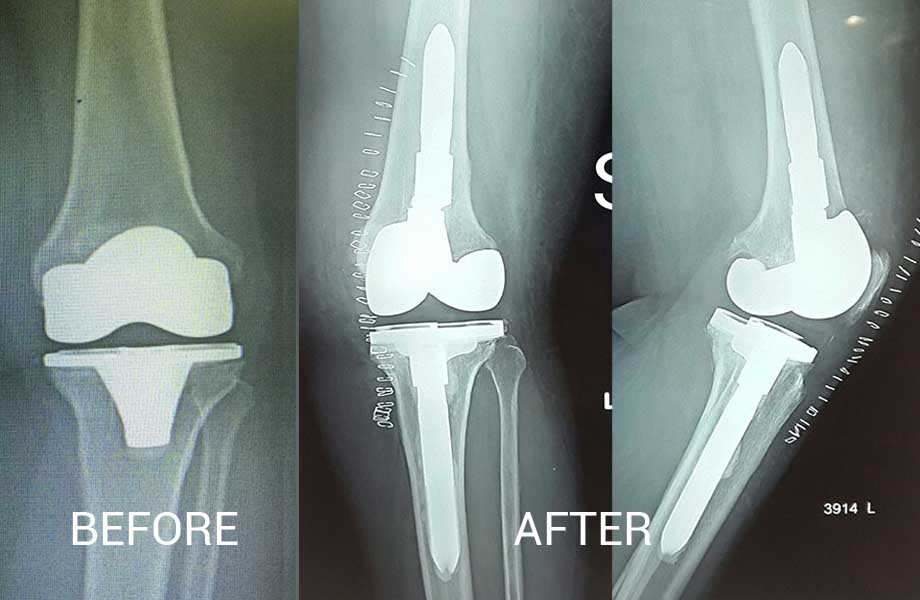

Total Knee Replacement